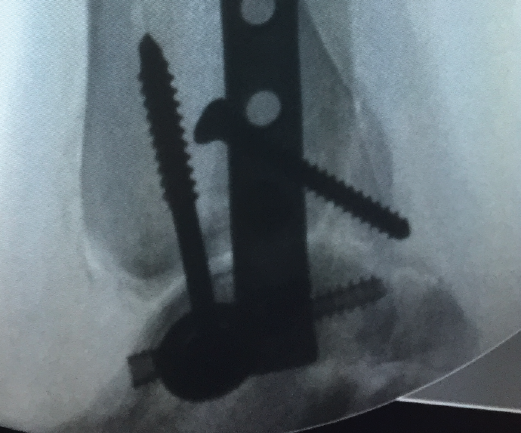

Figura 5. Control por radioscopia del aloinjerto.

- Tallado del injerto de manera intraoperatoria (Figuras 4 y 5).